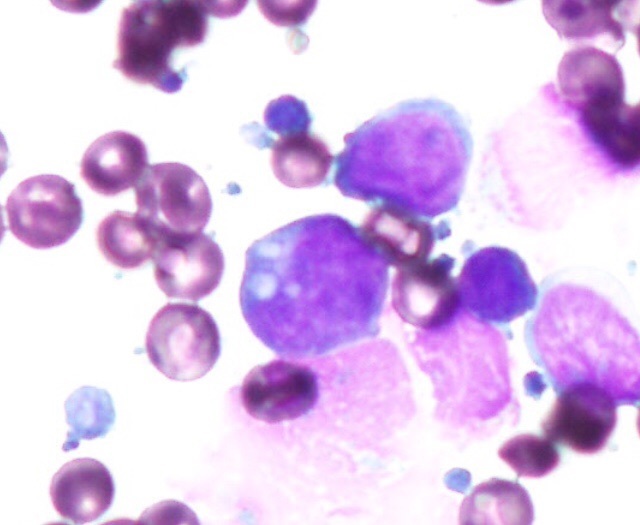

身体中にあるリンパ球ががん化する病気のリンパ腫。ヒトでは悪性リンパ腫と言われます。わんちゃん、ねこちゃんでは最も多い腫瘍の中の一つです。わんちゃんでは体の表層のリンパ腺が腫れる多中心型リンパ腫が最も多く、最近では胃腸にできる消化器型リンパ腫や皮膚・粘膜にできやすい皮膚型リンパ腫も増えているようです。ねこちゃんでは胃腸にできる消化器型リンパ腫にかかる場合が多く、他にも鼻にできる鼻腔型や胸の中にできる縦隔型などもあります。

リンパ腫のタイプによって治療法は異なりますが、抗がん剤を使った化学療法や局所的なものには放射線療法、抗がん剤と併用して免疫療法も行われます。

猫の消化器型高分化型リンパ腫。

高齢のねこちゃんで多い胃腸のリンパ腫。特にこの高分化型リンパ腫ではお薬の治療で長期にがんを抑えて普通の生活を送れることが多いです。

case.1

雑種猫、9歳齢、不妊雌。慢性の下痢、体重減少。組織生検にて高分化型リンパ腫の診断。

chlorambucil、predonisoneの内服治療。

症状消失、長期寛解生存。

case.2

case.1

結腸から直腸に発生した未分化型リンパ腫。

ミニチュアダックスフント、8歳齢、避妊雌。

肛門からの脱腸を繰り返し、結腸粘膜の組織生検で未分化型リンパ腫と診断。

L-CHOP療法を中心とした多剤併用化学療法を実施。寛解するも早期再燃し、ACNU、CCNU、DTICでサルベージ療法を実施。

結腸に発生した犬の高分化型リンパ腫。

雑種犬、9歳齢、避妊雌。組織生検による病理組織診断により高分化型リンパ腫と診断。

melphalan 0.05mg/kg sid-eod、predonisolone 0.5-1.5mg/kg sid 内服による治療で寛解。